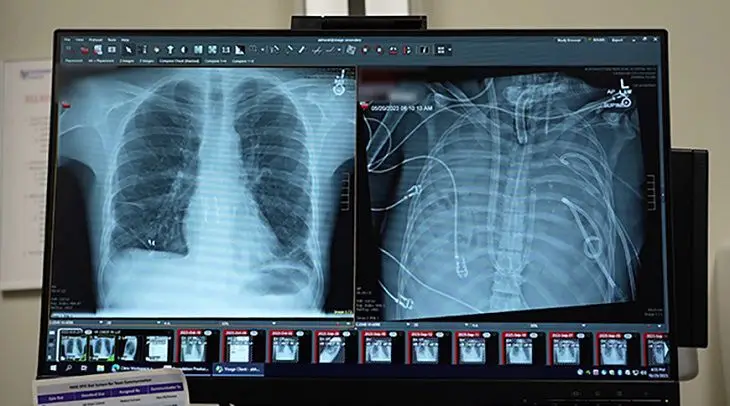

Болезнь стремительно переросла в дыхательную недостаточность, осложненную двусторонней пневмонией, сепсисом и острым респираторным дистресс-синдромом.

Инфекция, захватившая легкие, не поддавалась терапии, превратив органы дыхания в смертоносный очаг, отравляющий весь организм.

Эта сложная экстракорпоральная технология взяла на себя функцию газообмена, насыщая кровь кислородом и удаляя углекислый газ, одновременно регулируя кровоток и снимая фатальную нагрузку на сердце.

Сорок восемь часов пациент существовал в состоянии, ранее считавшемся невозможным для жизни. Его кровь обогащалась кислородом вне тела, пока команда врачей вела борьбу за его будущее.